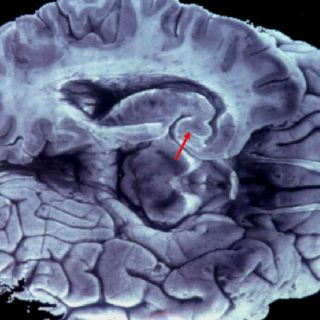

LONDRES, INGLATERRA (06/ENE/2012).- La pérdida de memoria y otras funciones cerebrales puede comenzar a los 45 años, lo que implica un gran desafío para los científicos que buscan nuevas formas de detener el avance de la demencia en la población, informaron investigadores.

El hallazgo de un estudio de 10 años de duración sobre más de siete mil trabajadores estatales de Gran Bretaña contradice las teorías previas de que el deterioro cognitivo no se inicia antes de los 60 años y podría tener implicancias de largo alcance en la investigación de la demencia.

El equipo de investigadores dirigido por Archana Singh-Manoux, del Centro para la Investigación en Epidemiología y Salud Poblacional de Francia y del University College de Londres, halló un deterioro modesto en el razonamiento mental en hombres y mujeres de 45 a 49 años.

Entre los sujetos de más edad del estudio, el deterioro promedio en la función cognitiva fue mayor, pero hubo una amplia variación en todas las edades. Un tercio de los individuos de 45 a 70 años no mostró deterioro durante el período estudiado.